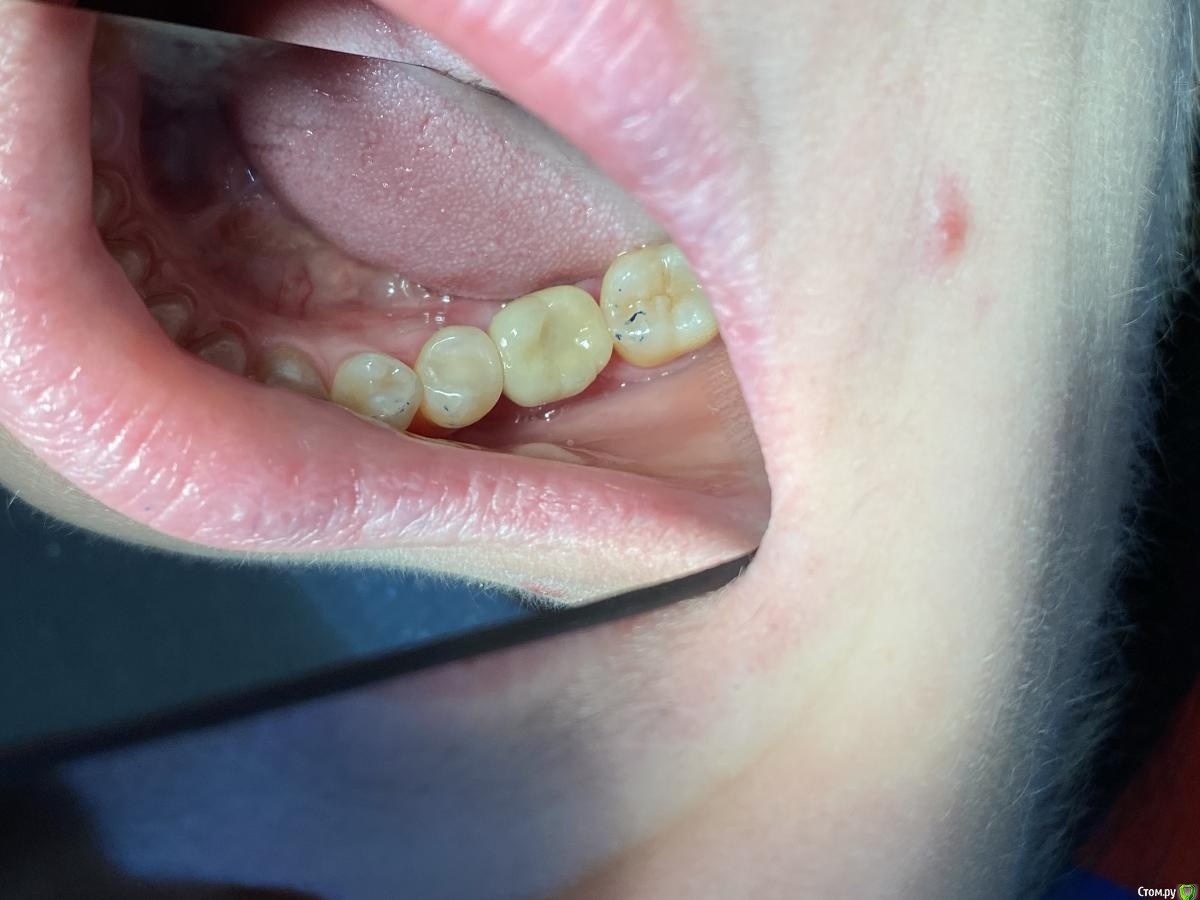

Женька Опубликовано 14 сентября, 2020 Автор Поделиться Опубликовано 14 сентября, 2020 Ну как-то вот так... Ссылка на комментарий

Irouil Опубликовано 14 сентября, 2020 Поделиться Опубликовано 14 сентября, 2020 (изменено) Не идеально, конечно, но я бы отправил уже на протезирование так на Вашем месте, прикрепленка есть, кортикалка по шейку Если включать перфекциониста, то можно пончо сделать, но нужно отслоиться через прикрепление эпителиальное, нужно и увеличение, и тунельный острый инструмент или микро хирургическое лезвие, и навык. Испортить тут можно гораздо больше, чем улучшить Основание абатмента пониже и пошире просто взять и пациента натаскать на гигиену, все ок будет Изменено 14 сентября, 2020 пользователем Irouil 1 Ссылка на комментарий

Женька Опубликовано 14 сентября, 2020 Автор Поделиться Опубликовано 14 сентября, 2020 Не идеально, конечно, но я бы отправил уже на протезирование так на Вашем месте, прикрепленка есть, кортикалка по шейку Если включать перфекциониста, то можно пончо сделать, но нужно отслоиться через прикрепление эпителиальное, нужно и увеличение, и тунельный острый инструмент или микро хирургическое лезвие, и навык. Испортить тут можно гораздо больше, чем улучшить Основание абатмента пониже и пошире просто взять и пациента натаскать на гигиену, все ок будетЯ придерживаюсь этого же мнения...Я скорее испорчу то, что получилось. Эти фото с формирователем 4.5, 3 месяца ходили с 4.0На этапе прикручивания 4.5, пациентка отметила легкое жжение... на фдм метрогил был...вот думаю, то ли это на метрогил такая реакция, то ли я что-то задавил? Планировали на тибейзе geo делать... там варианта пошире насколько я знаю нет. 4.5 и размеры по вертикали cut и длинные З.Ы. Вчера у Ильгама Ирековича на курсе впервые познакомился с галилеями от экзама... всего 2.8, быстро привыкли глаза (учитывая, что они не индивидуально под меня были)... это просто какой-то другой мир. Ссылка на комментарий